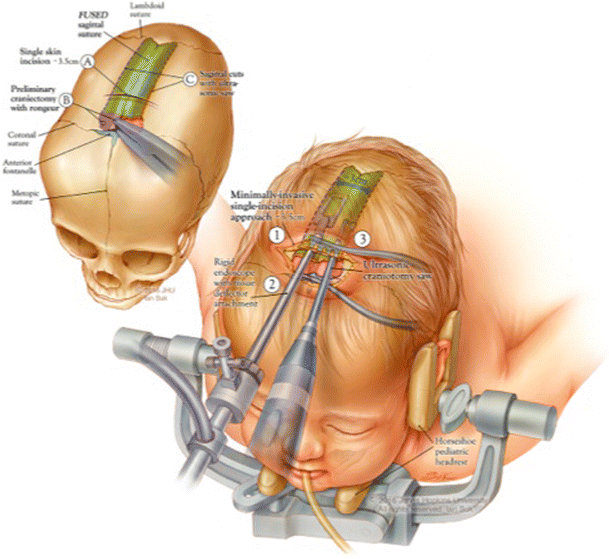

جراحة الدرز السهمي بالمنظار عند الأطفال: شرح كامل للعملية والنتائج المتوقعة يُعد التحام عظام الجمجمة المبكر من الحالات التي تقلق الكثير من الأهل، خاصة عند ملاحظة أن شكل رأس الطفل أصبح طويلًا وضيقًا بشكل

جراحة التحام عظام الجمجمة بالمنظار (Endoscopic Craniosynostosis Repair): دليل شامل للأهل يُعد التحام عظام الجمجمة المبكر من الحالات التي قد تثير القلق لدى الأهل، خاصة عند ملاحظة تغيّر شكل رأس الطفل في الأشهر الأولى